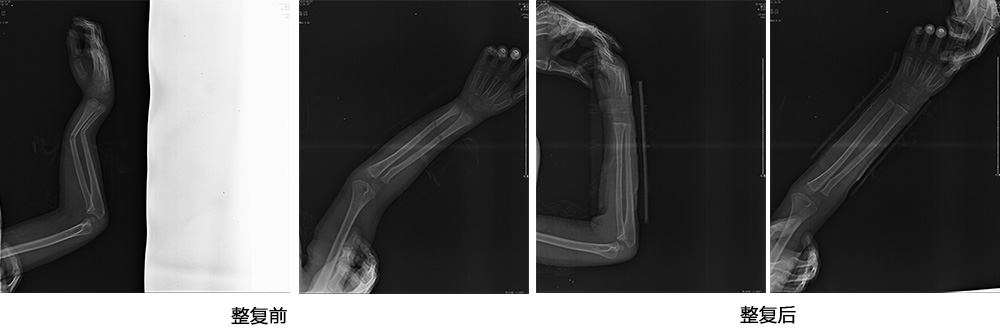

傳統(tǒng)手法整復(fù)病例影像

CR99142